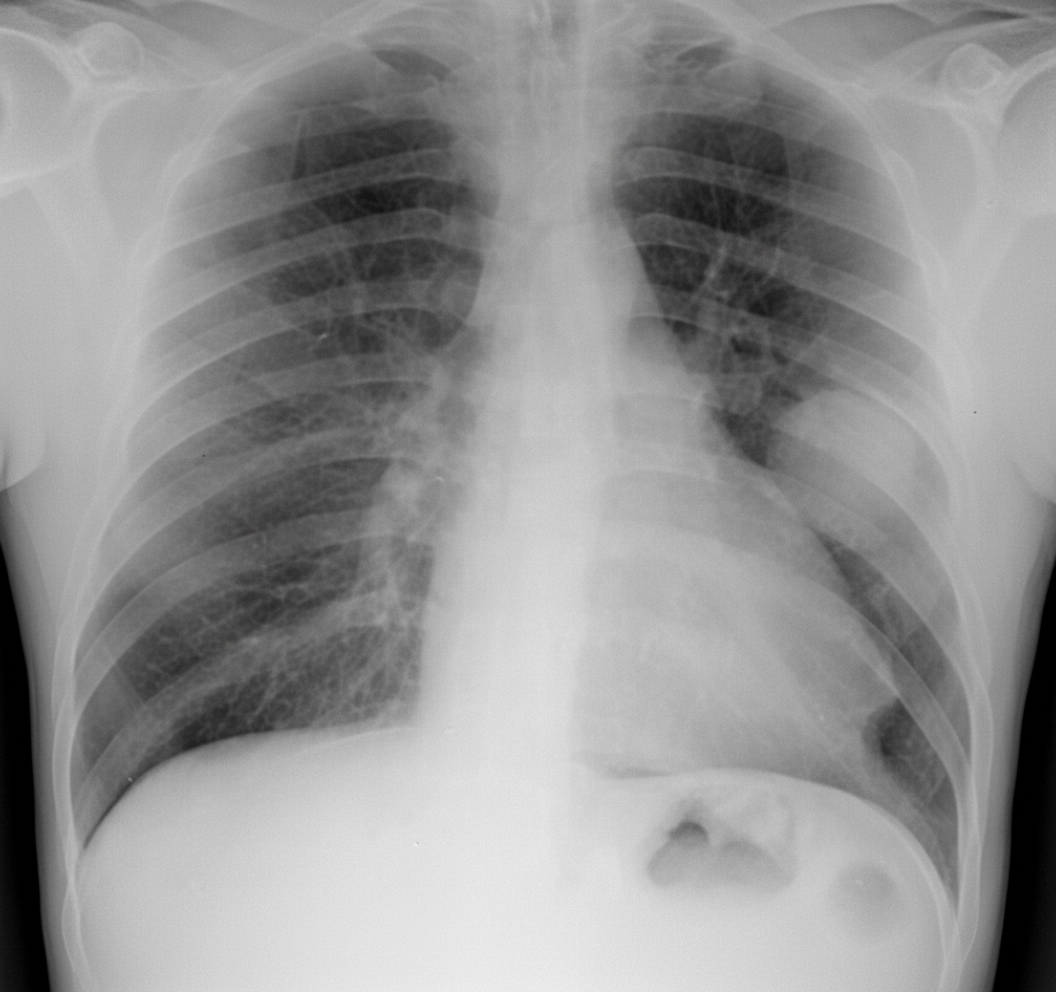

A 60-year-old man with a past history of smoking for 30 years (he stopped 3 years ago, prior to cardiac bypass surgery) is admitted with cough and mild hemoptysis. He is afebrile with no shortness of breath. Physical exam is negative except for rhonchi in the left upper lung zone on auscultation. What is the finding or abnormality most likely to occur with the lesion seen on the chest X-ray?

Explanation: ***Serum calcium of 13.6 mg/dL*** - **Squamous cell carcinoma** of the lung commonly causes **hypercalcemia** through **PTHrP (parathyroid hormone-related protein)** secretion as a paraneoplastic syndrome. - The clinical presentation of a **heavy smoker** with a **left upper lobe mass**, cough, and hemoptysis strongly suggests squamous cell lung carcinoma. *Sputum positive for fungal elements* - **Fungal infections** typically present with **fever** and **systemic symptoms**, which are absent in this afebrile patient. - The patient's **smoking history** and **unilateral upper lobe lesion** make malignancy more likely than fungal infection. *Increased D-dimer levels* - **D-dimer elevation** is associated with **pulmonary embolism** or **deep vein thrombosis**, but this patient has no **dyspnea** or chest pain. - The **localized rhonchi** and **hemoptysis** point to a **parenchymal lung lesion** rather than vascular pathology. *Koilonychia* - **Koilonychia (spoon-shaped nails)** is a sign of **chronic iron deficiency anemia**, not typically associated with lung masses. - While lung cancer can cause anemia, **koilonychia** develops over months to years and is not an acute finding with lung malignancy.